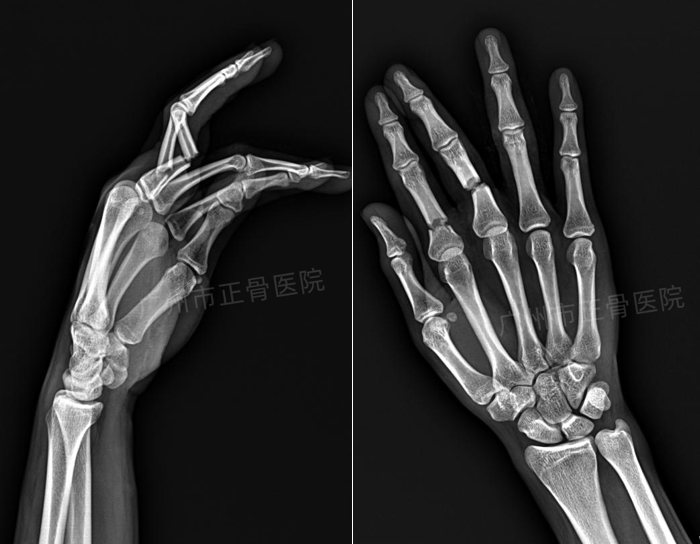

治疗:行手法复位后石膏托外固定治疗。复位后复查X片示骨折端对位对线较前明显改善。嘱患者定期复诊(每周一次),定期复查X线了解骨折情况。4周后复查X线提示骨痂生长,骨折端稳定,予拆除外固定,指导患者进行关节功能康复锻炼。7周后患者手指活动基本恢复正常。

▲复位后,骨折端对位对线良好